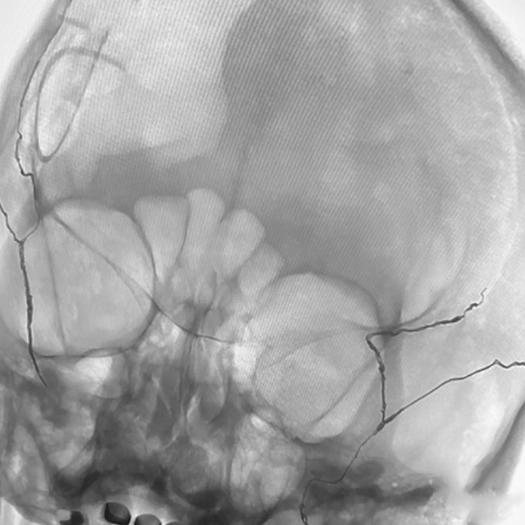

Proximal vessel sacrifice of LICA/LECA using POD400, PAC400, and PC400. A total of 877 cm of coil delivered by ACCESS25

Vessel Sacrifice

• POD400 + PAC400 for vessel sacrifice

• .020″ platform offered high volume and flexibility in case

• POD400 created a backstop, filled with PAC400

• BMX81 designed for stable vascular access